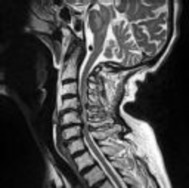

Preoperative MRI images are shown from a 67-year-old woman with neck pain, bilateral upper extremity paresthesias, progressively worsening balance, several falls, and increasing problems in both hands with dropping objects. Figure 1 is a sagittal view, Figure 2 is an axial cut at C2-3, Figure 3 is an axial cut at C5-6, and Figure 4 is an axial cut at C6-7. The patient’s motor strength is grade 4+ of 5 in the bilateral upper extremities.

What is the best next step?

4. Posterior decompression and fusion Discussion: D

The patient has degenerative changes with central and foraminal stenosis from C2-7, including spinal cord compression at C2-3, C5-6, and C6-7. Her progressively worsening balance, falls, and clumsiness are consistent with cervical spondylotic myelopathy. Given the progressive nature of the neurologic symptoms, surgery is recommended for patients with worsening

symptoms. Physical therapy potentially could provide pain relief but would not address the spinal cord compression. Cervical epidural steroid injection is not recommended because of the increased neurologic risk in the setting of substantial spinal cord compression. Given the multiple levels involved and the extension to the C2-3 level, an anterior approach would increase the risk of morbidity and pseudarthrosis compared with the posterior approach, which would allow adequate decompression of the central and foraminal stenosis.

Surgery for cervical myelopathy is performed to decompress the spinal cord, stabilize the spine, and prevent further neurologic injury. Most patients obtain considerable pain relief and some improvement in balance and clumsiness, depending on the severity of the symptoms. Complete resolution of all symptoms should not be expected.